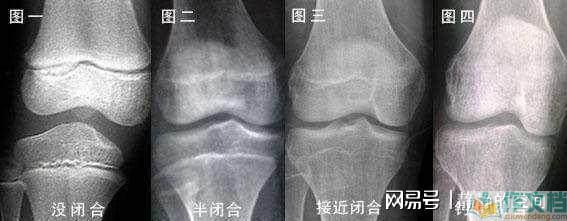

3、看孩子骨骼线

这是指孩子长骨干骺端与骨骺之间的一层软骨结构,又称为骺板,会随着年龄的增长而慢慢缩短,而在它完全闭合后,骨干就会和骨骼连为一体,骨骼钙化,骨骼线消失,就无法长高了。

因此家长如果实在担心,可以去医院拍张X光片,它呈现为一条较宽的透明带,如果没有闭合就说明尚有生长空间,家长还可以努力。